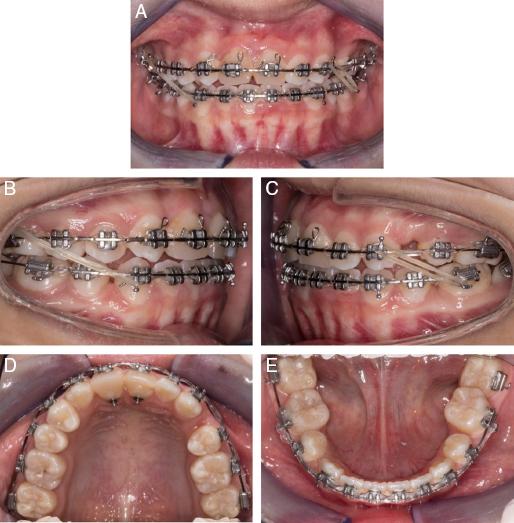

Six months later, a clinical and radiographic examination confirmed the absence of pulpal pathology and complete root development of the transplanted teeth. Fixed orthodontic appliances were placed on the upper and lower arches for levelling and alignment. Once in 0.019˝ × 0.025˝ stainless steel wires, the patient was instructed to wear asymmetric inter-arch elastics to help with the correction of upper and lower midlines and space closure (Figure 10A-E). After 28 months of active orthodontic treatment, all of the fixed appliances were removed, and the prosthodontist was able to add direct composite resin restorations onto #13 to #23 for aesthetic camouflage. Upper and lower removable vacuum-formed retainers were worn on a night-time basis.

(A-E) Midtreatment intra-oral photographs.